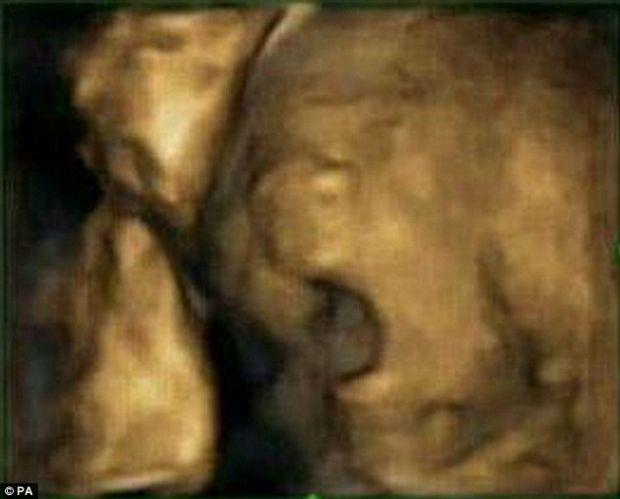

Bebeğin esneme anı

Bu ultrasonlardan birinde ise ilginç bir görüntü yakalandı. Bebeklerden bir tanesi ana karnındayken esniyordu. Bu görüntü karşısında heyecanlarını saklamayan uzmanlar, bu teknik sayesinde bebeklerin doğmadan önceki gelişimi ve beyin fonksiyonları hakkında daha iyi bilgiler sağlayabileceklerini düşünüyor.